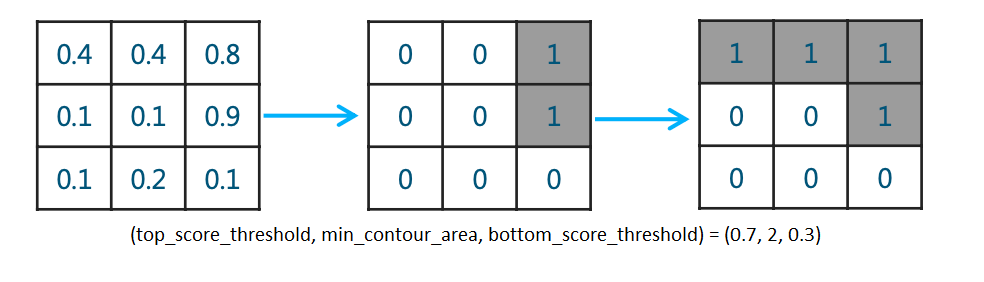

而作者在此基础上作了改进,使用了三重阈值(top_score_threshold, min_contour_area, bottom_score_threshold)的方法来达到相同的目标,且称改进后的方法为Triplet.其具体逻辑为:当大于概率阈值top_score_threshold的pixel数少于

min_contour_area,就将此mask pixel值全部置0,也就是认为此胸片没有气胸,然后再使用阈值bottom_score_threshold产生真正的mask。简单画个示意图如下:

最终作者通过搜索,分别获得了在validation和在Public Leaderboard上的最优参数:

- Best triplet on validation: (0.75, 2000, 0.3).

- Best triplet on Public Leaderboard: (0.7, 600, 0.3)

最后再附上作者的代码:

classification_mask = predicted > top_score_threshold

mask = predicted.copy()

mask[classification_mask.sum(axis=(1,2,3)) < min_contour_area, :,:,:] = np.zeros_like(predicted[0])

mask = mask > bot_score_threshold

return mask